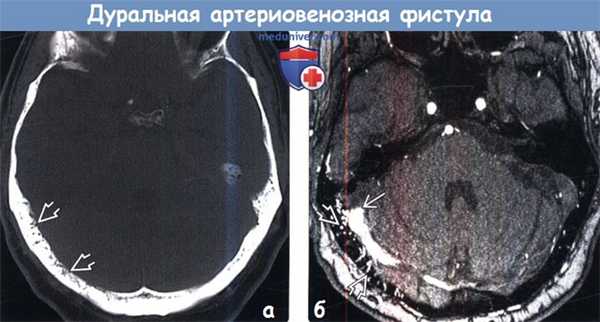

(Справа) Сагиттальный срез, Т2-ВИ: диффузная гиперинтенсивность сигнала продолговатого мозга и верхнешейного отдела спинного мозга. (Слева) Аксиальный срез, FLAIR МР-И головного мозга: признаки патологических изменений на уровне ствола мозга в виде гемосидериновой окраски каудальных ядер ствола мозга, скорее всего связанной с перенесенным ранее кровоизлиянием.

(Справа) Сагиттальный срез, Т1-ВИ с КУ: диффузное контрастное усиление продолговатого мозга и верхнешейного отдела спинного мозга. Диффузный характер контрастного усиления с нечеткими границами на протяжении нескольких сегментов для очагового (опухолевого) поражения нетипичен. (Слева) На ангиограмме наружной сонной артерии контрастирована фистула, кровоснабжаемая отчасти средней менингеальной артерией и дренирующаяся в венозное русло Причиной шейной миелопатии может быть венозная гипертензия спинного мозга на фоне венозного сброса от интракраниальной фистулы.

(Справа) В позднюю артериальную фазу после контрастирования наружной сонной артерии визуализируется фистула, кровоснабжаемая отчасти средней менингеальной артерией и дренирующаяся в спинномозговой канал.д) Клинические особенности: